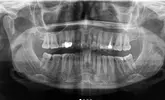

Mesleki ilgi alanları gülüş tasarımı, lamine veneer ve zirkonyum kaplamalar, implant üstü protezler (all-on4 & all-on6 hibrit protezler), tüm takılıp çıkartılabilen ( hareketli protezler ) diş beyazlatma, diş sıkmaya bağlı eklem hastalıkları ve botoks uygulamaları , şeklinde multidisiplinerdir.